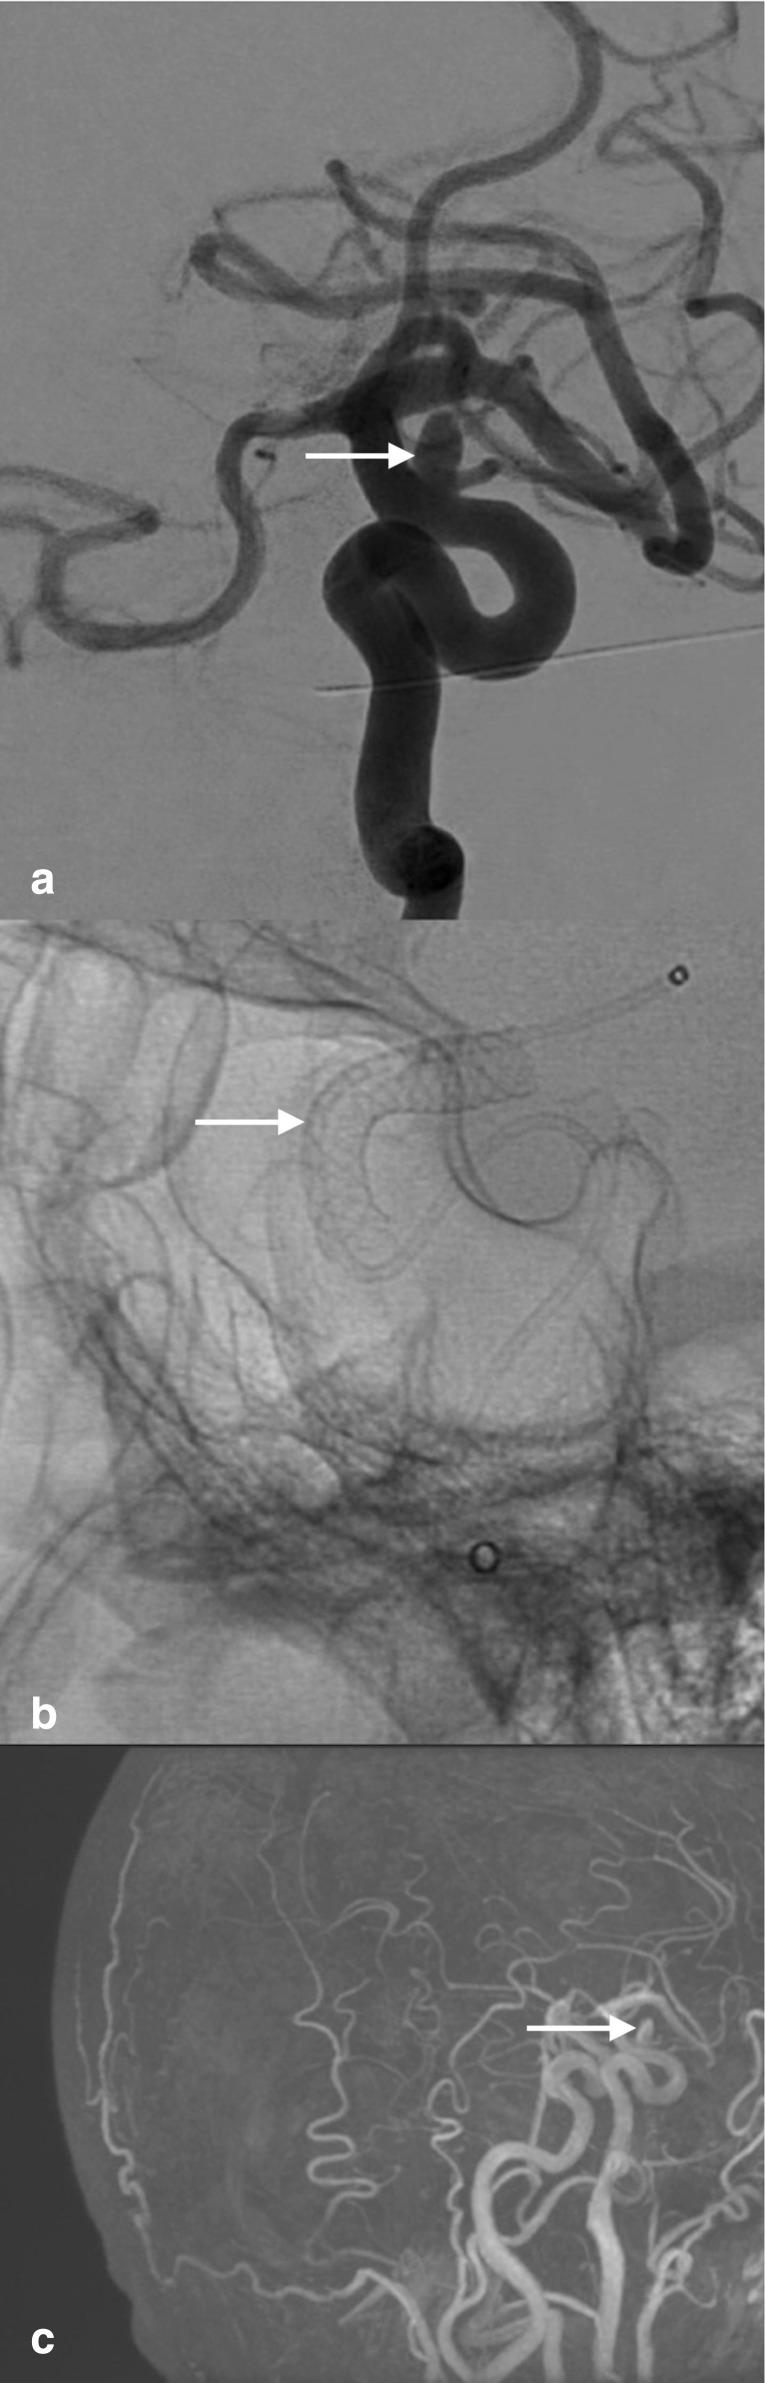

The transradial approach has gained popularity in the neuroendovascular field after several studies proved its low rate of hemorrhagic and vascular-related complications in both diagnostic and therapeutic procedures. This is a case of a patient who presented for flow diversion treatment of an incidental left carotid ophthalmic aneurysm. The procedure was uneventful. Post-operatively, the patient's neurological exam and vital signs were normal, however the patient complained of abdominal and chest pain that worsened when lying down and improved when sitting up. Radiologic diagnosis confirmed the presence of a thyrocervical trunk pseudoaneurysm which was completely obliterated with Onyx 18 embolization. Thyrocervical trunk pseudoaneurysm formation is a rare complication of the transradial approach. Shedding the light on these entities is essential as symptoms vary in severity and presentation and necessitate swift diagnosis and treatment.

在多项研究证明经桡动脉途径在诊断和治疗操作中出血及血管相关并发症发生率较低后,该途径在神经血管内介入领域已越来越受欢迎。本文报告一例因偶然发现的左侧颈内动脉眼动脉瘤而接受血流导向治疗的患者。手术过程顺利。术后,患者神经学检查及生命体征正常,但患者主诉腹部和胸部疼痛,平卧时加重,坐起时缓解。影像学诊断证实存在甲状腺颈干假性动脉瘤,通过使用Onyx 18进行栓塞,该假性动脉瘤完全闭塞。甲状腺颈干假性动脉瘤形成是经桡动脉途径的一种罕见并发症。了解这些情况至关重要,因为其症状的严重程度和表现各不相同,需要迅速诊断和治疗。